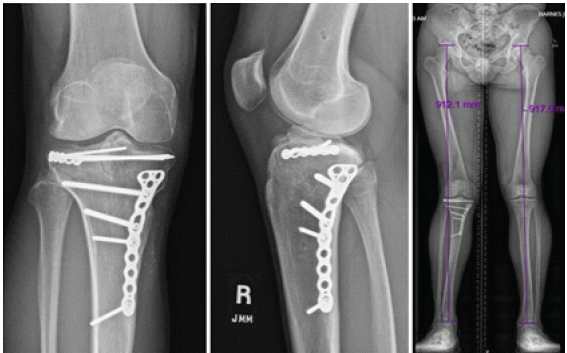

On post-injury day 8, the patient returned for removal of external fixator and definitive fixation. The medial side was addressed first through a posteromedial approach. After direct open reduction, a small fragment plate was used to buttress the medial condyle with all fixation performed distal to the physis. Attention was then turned to the lateral side where a standard anterolateral approach was made, centered over Gerdy’s tubercle. A femoral distractor was applied for lateral joint visualization and a submeniscal arthrotomy was performed. The flipped articular fragment was noted to be trapped between the femur and the tibia. When this piece was rotated anteriorly, the torn lateral meniscus was revealed and noted to be impacted into the tibial metaphysis. The articular fragment was reduced and held with Steinmann pins. A minifragment plate was then contoured as a rim plate and screws were inserted to raft and secure the articular fragment as well as the medial epiphysis. All lateral fixation was proximal to the physis (Fig. 3). The lateral meniscus was then repaired using an all-inside device posteriorly and open repair to the lateral plate for the remainder of the body. Following fixation, the knee was ligamentously stable on examination.

Figure 3: Final intraoperative fluoroscopic images following fixation: All lateral fixation was kept proximal to the physis and all medial fixation distal to the physis.